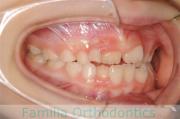

No.22V-210

- 下顎前突

- 欠損歯

- 32歳

- 女性

- 抜歯部位

- 上:

- 8448欠

- 下:

- 主な使用装置:

- FEA 022

- 治療にかかった費用:

- 保険

かみ合わせが悪い、顎が出ているのを治したいと来院されました。驚くことに、これまで小児期から成人にかけて3回も矯正治療を行っており、歯根吸収も著しい骨格性の受け口ということで、大変な難症例でした。2年半、30回程度の通院が必要でした。

外科的矯正治療には、矯正治療単独で行った場合のリスクや副作用に加えて、外科手術のもつリスクがあります。全身麻酔や入院の必要性、術後の疼痛や顔の腫れ、手術部位周囲の感覚麻痺などがそれにあたります。

厚生労働省のガイドラインを守るために書くのならば、この症例のリスクは前記のようになるでしょうが、このケースに関しては「骨格のズレを度外視?もしくは見逃し?して矯正治療を行うことのリスク」が最大限に表れていると言えるかもしれません。